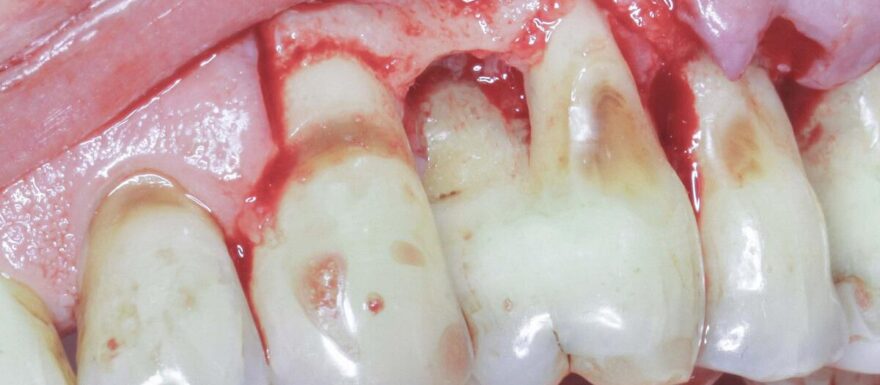

Chirurgie kan na een initiële parodontale behandeling noodzakelijk zijn om verdere pocketdieptereductie te realiseren. In deze nascholing leert u wanneer een chirurgische benadering zinvol is en welke patiëntgebonden en lokale factoren bepalend zijn voor het behandelresultaat. Denk aan mondhygiëne, rookgedrag, medicatiegebruik, maar ook aan anatomische kenmerken op gebitselementniveau.

De nascholing behandelt twee hoofdbenaderingen: resectief en regeneratief. U krijgt inzicht in de verschillen tussen beide strategieën en leert welke technieken en materialen daarbij toegepast worden. Ook wordt er aandacht besteed aan flapsluiting, waarbij de positionering afhankelijk is van de gekozen chirurgische benadering.